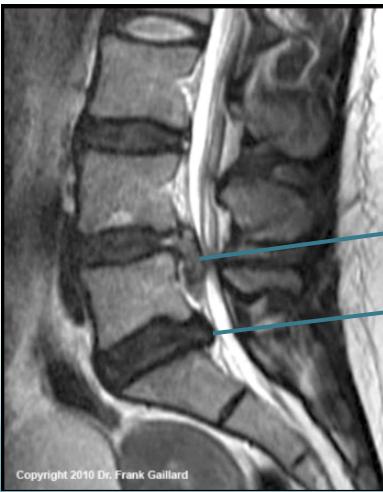

MRI:

- Gold standard for identifying disc pathology and localizing lesions

- Shows:

- Disc sequestration

- Disc bulge/protrusion

- MRI:

- Gold standard for disc identification and lesion localization